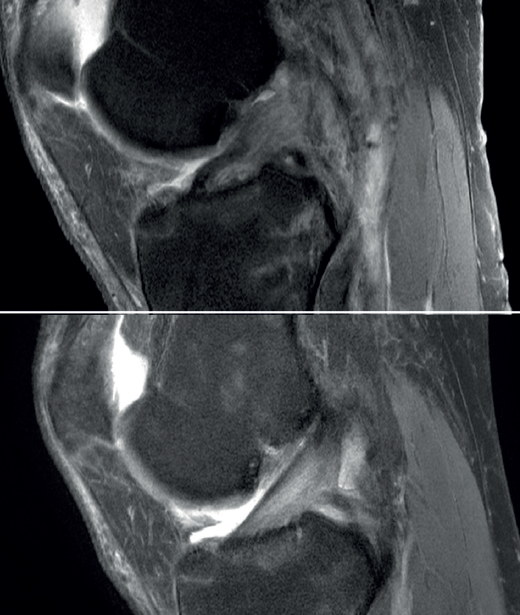

Figura 1. Rotura de ligamento cruzado anterior (LCA). A: imagen sagital de resonancia magnética (RM) de rotura aguda al diagnóstico; B: control de RM a los 12 meses de evolución con tratamiento conservador con evidente mejoría en la imagen del ligamento.